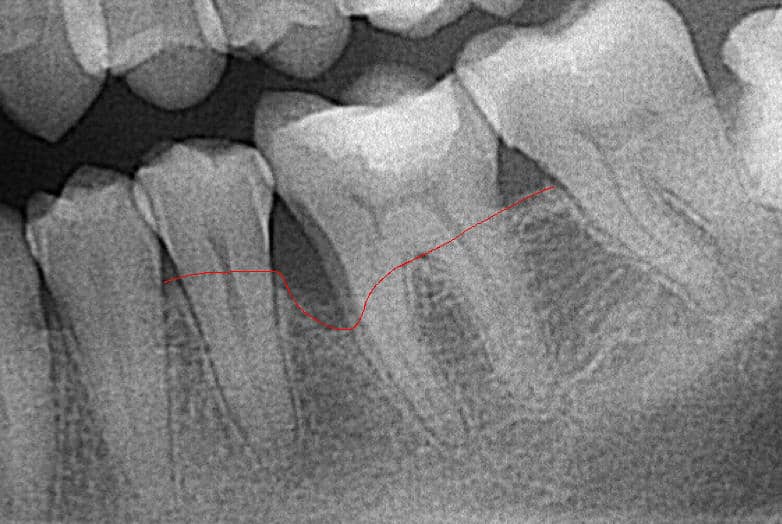

Az alábbi képen jól látszódik a csonthiány.